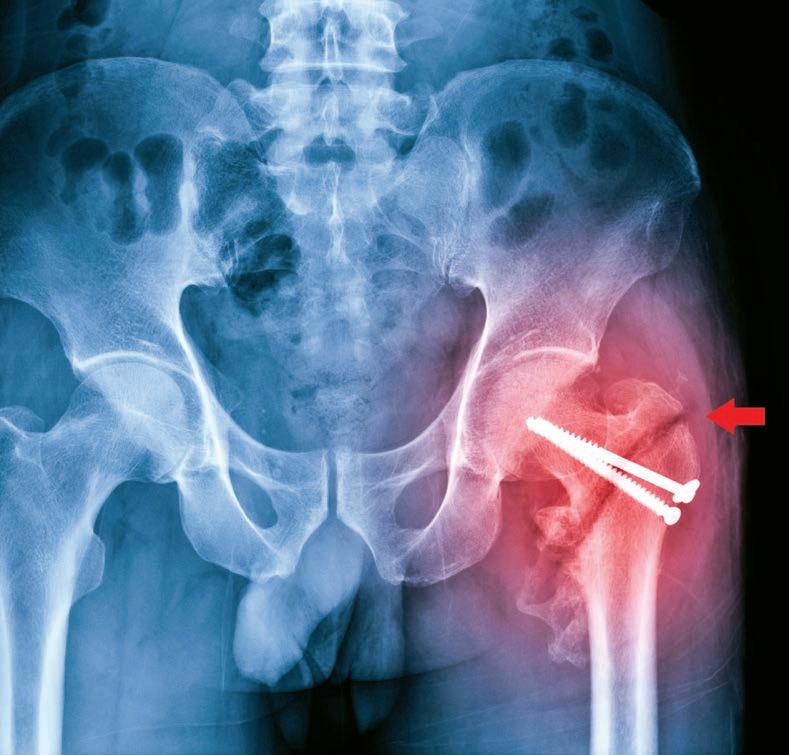

Getting hip about early care

Every year, more than 19,000 Australians – many of them elderly –fracture their hip. Now revised guidelines are aimed at ensuring they get more timely treatment.

Esperance woman Jill Bower, post-hip surgery

WA geriatrician Dr Hannah Seymour knows only too well that time can be the enemy when treating people who break their hip, particularly when facing geographical barriers.

Based at Fiona Stanley Hospital, her experience of working closely with older patients who have had a hip fracture means Dr Seymour understands that prompt surgery reduces pain, speeds recovery and reduces time spent in hospital.

Yet as hip fracture surgery can only be performed at larger hospitals with suitable facilities, some people in regional and remote areas have to be transferred long distances. In 2022, 14% of hip fracture patients in Australia were transferred from another hospital for their surgery.

However, updated guides for the care of hip fractures are now calling for hospitals to move more quickly to get patients into theatre – and up walking after their surgery.

The Australian Commission on Safety and Quality in Health Care (ACSQHC) launched a revised national clinical care standard for hip fracture in September at the binational Hip Fest 2023 conference, hosted by the Australian and New Zealand Hip Fracture Registry.

Cut the wait

The standard was first launched in September 2016 to guide consumers, clinicians and health services on delivering appropriate care to people with a hip fracture. The revised standard reduces the recommended maximum time to surgery, along with other improvements for better care.

The commission said many people with a hip fracture were waiting longer than was optimal for surgery, despite some hospitals making big improvements in the past few years.

Australia’s ageing population made improvements to hip fracture care even more important, as most fractures occur in people aged over 65 who are more vulnerable to complications.

Hip fracture significantly increases an older person’s risk of death, with one in four people dying within 12 months. Of those who survive,

many lose their ability to live independently or return to their former lifestyle.

The updated standard for hospitals has reduced the maximum time to surgery from 48 hours to 36 hours, in line with international guidelines. For the first time, this explicitly includes patients who need to be transferred to a hospital that can perform the surgery.

Network needed

The revised standard calls on healthcare services to build effective systems and networks with other facilities to ensure coordinated transfer and help all patients receive timely surgery. For Dr Seymour, this change in the standard will be a key driver to improve time to surgery for all patients.

“Nationally, we haven’t reduced our average time to surgery and are failing patients. It is disappointing and needs to change because frail, older people are lying in hospitals in pain for longer than they need to be.

“We know that it is possible to reduce the time to surgery if you have the right systems in place,” she said.

“We’ve shown in WA that it often takes just as long for a patient being transferred for surgery from a hospital 45 minutes away by car, as it does for someone flown in from hundreds of kilometres away. It doesn’t matter where you transfer from, all patients are waiting, even if they are just down the road.”

Dr Seymour has long advocated for older people needing a transfer to a larger hospital for hip surgery. WA Health has streamlined interhospital transfer, so there are now clear arrangements for hospitals in smaller WA towns to know where they need to transfer the patient.

The ACSQHC’s acting chief medical officer, emergency physician Associate Professor Carolyn Hullick , said there was an urgent need for health services to offer better care for

people with a hip fracture, using the framework in the updated standard.

“Anyone who has seen someone live through a hip fracture knows it’s much more than a broken bone,” she said. “People with a hip fracture tend to be older, frail and more vulnerable, so it is critical the fracture is repaired quickly to reduce pain and get them on the road to recovery and back to independence.

“The data is sobering, as an Australian with a hip fracture is almost four times more likely to die within a year than someone of the same age who isn’t injured. This has an immense personal toll on individuals and families, in addition to the burden on our health system of around $600 million each year.”

Much has improved since the Hip Fracture Clinical Care Standard was introduced in 2016, according to ANZHFR annual reports, with 91% of hospitals performing hip fracture surgery in Australia participating to help improve their hip fracture care.

An evaluation of the standard in 2020 found that 98% of respondents reported that the standard improved care when implemented by their organisation; and 96% of respondents said the standard was relevant to their practice.

Times vary

But while some hospitals had substantially reduced their time to surgery, there was still marked variation.

In 2022, the average time to surgery ranged from 16 to 92 hours, with the longest waiting times for people being transferred for surgery. About 78% of patients had surgery within 48 hours.

Geriatrician Professor Jacqueline Close, Co-Chair of the ANZHFR and the expert advisory group for the standard, believes the updated standard will be a lever for change.

“The Hip Fracture Clinical Care Standard sets expectations for how every patient should be cared for, while allowing for treatment to be tailored to the individual,” she said.

“The adage ‘don’t let the sun set twice before hip

continued from Page 23

fracture repair’ has merit. No one wants to see their mum or dad fasting and in pain waiting for surgery; and shorter time to surgery is associated with fewer complications, better recovery and survival.

“It is also more cost efficient to manage these patients well. Every day surgery is delayed, two days are added to the length of stay. The sooner you operate, the quicker patients can get walking and go home.”

Professor Close said the registry data showed Australia could do better in several key areas of hip fracture care. “The evidence tells us the sooner you are supported to get out of bed, the better your functional recovery. Last year, fewer than half of patients walked on the first day after hip fracture surgery.

“Also, only one third (32%) of patients leave hospital on bone protection medication for osteoporosis to prevent another fracture. We absolutely can and should do better,” she said.

For 85-year-old Esperance grandmother Jill Bower, it was a relief to know she was in good hands when she arrived by ambulance at Esperance Hospital after fracturing her hip. The ED team swung into action to transfer Jill from the coastal town to Fiona Stanley nearly 700km away, with the Royal Flying Doctor Service.

“At Esperance they gave me the nerve block in my groin for pain before they moved me, which was great,” she said. “Early the next morning they put me on the RFDS flight, and I arrived in Perth by midday. I went straight to Fiona Stanley Hospital because they’d been warned – so I got a bed straight away, I didn’t have to wait.”

The whole process meant that Jill had surgery less than 48 hours after presenting to Esperance Hospital. The next day, she began her recovery under the care of Dr Seymour.

“They got me up the day after surgery on a tall frame and I felt good. Later they changed me onto

a four-wheel walker and had me walking up the hallways once a day, using the side rails to keep me moving.”

Jill completed her recovery in two smaller hospitals where she was able to build up her strength before heading home to Esperance on a regional flight.

Dr Seymour said that for a patient like Jill, Esperance was too small a place for surgery at the local hospital, but staff could deliver a nerve block and knew which hospital to call.

“The patient is put on our surgery list when they call, so are in the queue based on the time of fracture,” she said.

“Established communication channels are now in place, and much of the time we can operate in that 36-hour window because we have a system with transfer protocols and straight-to-ward arrangements.

“We have a partnership with the RFDS who know that Fiona Stanley Hospital wants to operate promptly

and that the patient is already on their list, even though they aren’t physically in the hospital.”

The WA Country Health Service team also worked hard with their emergency departments to ensure staff were well-trained to deliver a nerve block prior to moving patients, ensuring effective pain relief.

Dr Seymour said it was encouraging that 90% of hip fracture patients nationally now received nerve blocks before surgery, but sometimes only in the operating theatre. She supports the increased emphasis in the revised standard on patients receiving nerve blocks before transfer to decrease pain during transportation.